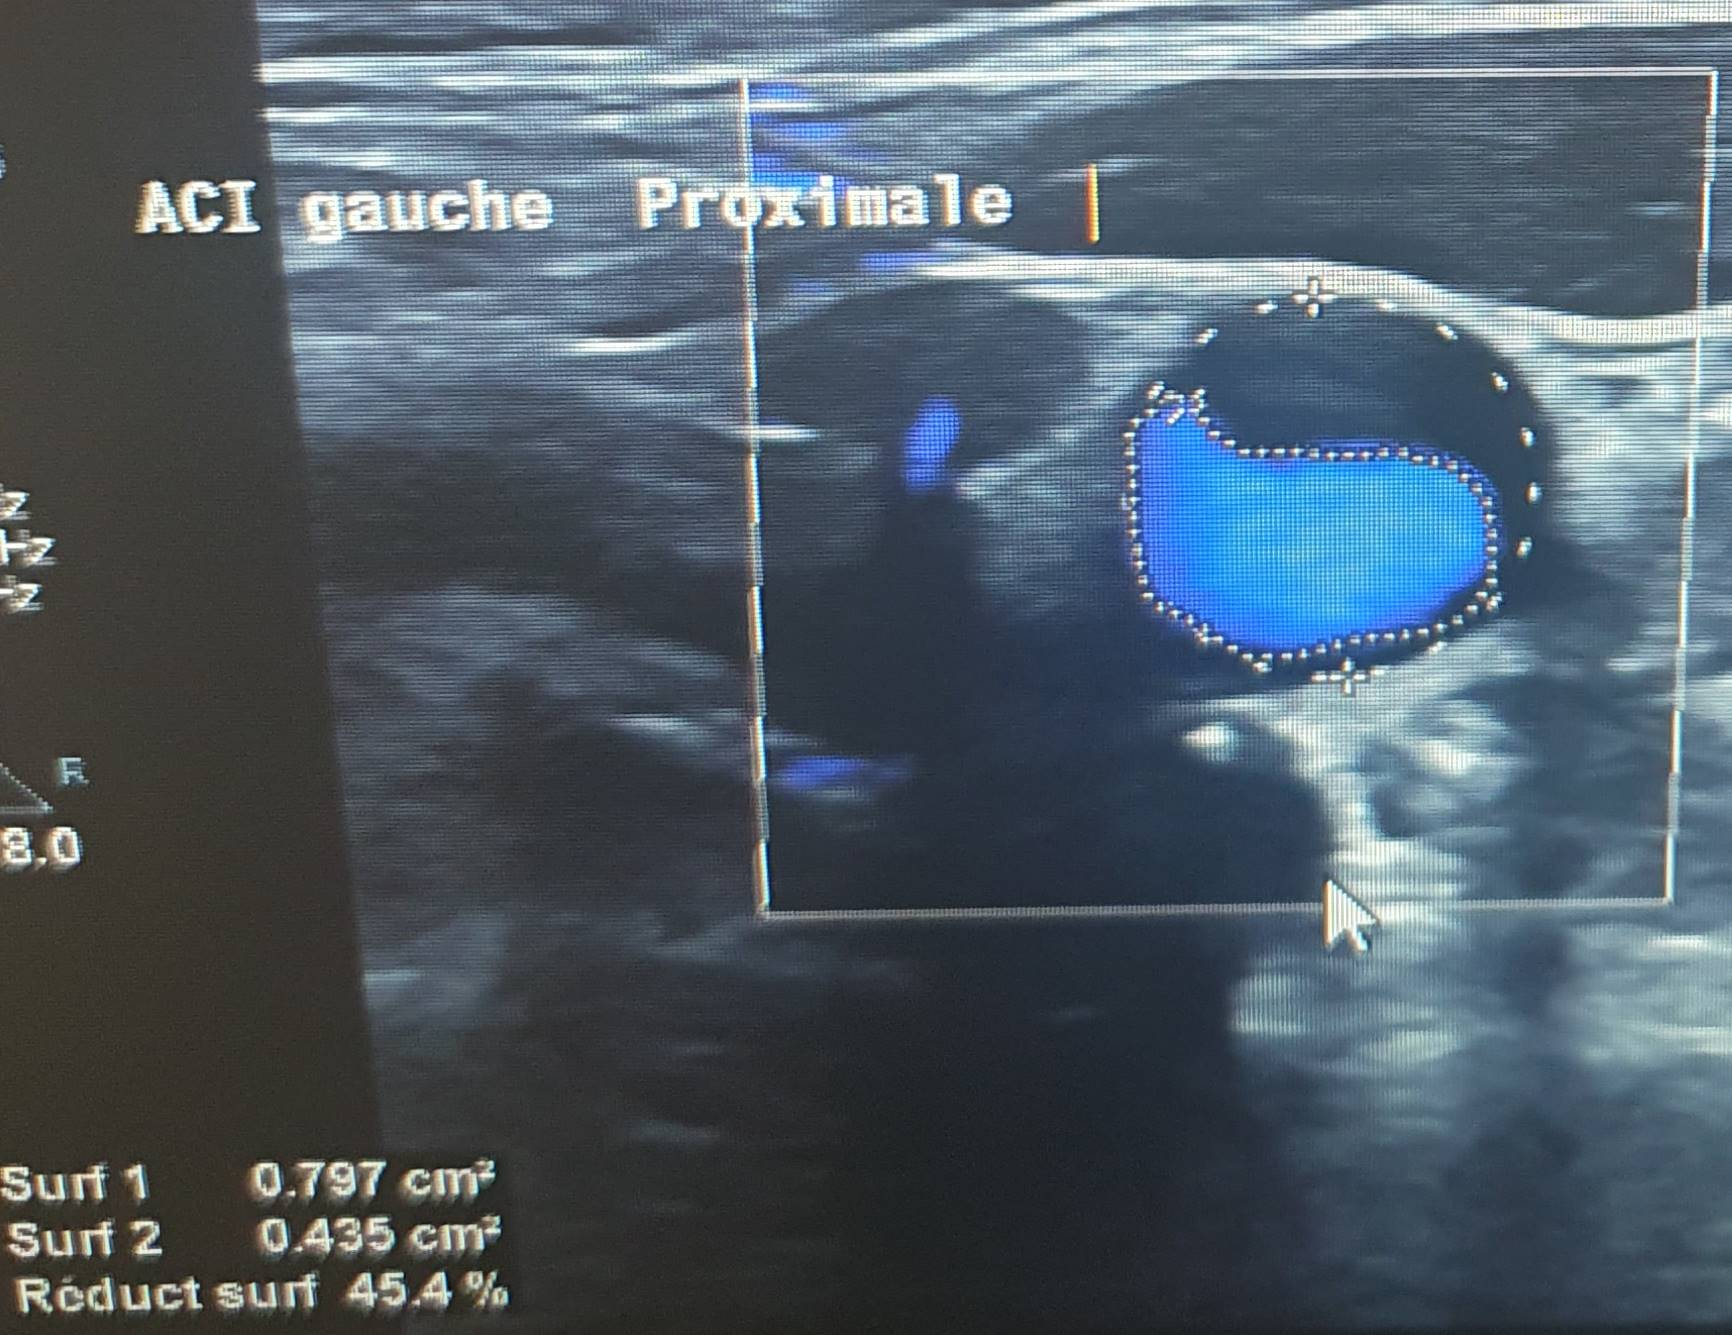

On the evolutionary level: complete regression of symptomatology on day 2 with NIHSS = 0. Ultrasound of ASD on day 3 shows the persistence of the thrombus without anatomical or hemodynamic modification. On day 7 (Figure 2) good anatomical regression of the stenosis to 45% without hemodynamic impact. D10 continued regression of the thrombus without character stenosing.

Figure 1. 70% stenosis of the CCG on day 1.

Figure 2. 70% stenosis of the CCG on day 7.